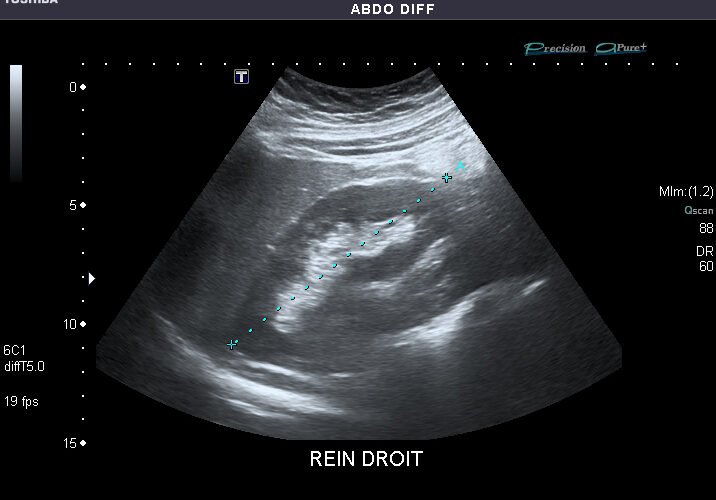

WEEK2 Day3 エコー by 村上 徹 · 公開 2024年10月11日 · 更新済み 2025年11月22日 From Abdominal Ultrasound – Wikipedia 昼前にエコーの講義。 プローブを落とすと壊れる 像ができる原理を押さえることが、正しく読影するポイント アーチファクトの現れる原理を知る カラードップラの色分けを勘違いしないように プローブに近づく向きが赤 プローブから遠ざかる向きが青 動脈と静脈ではない 関連